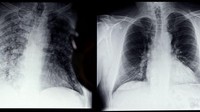

Lalu, ada foto rontgen dari paru-paru seorang perokok.